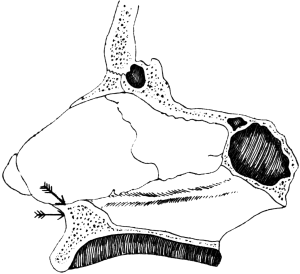

| 244. | Diagram to show the usual Points at which the Lateral Sinus is primarily infected | 442 |